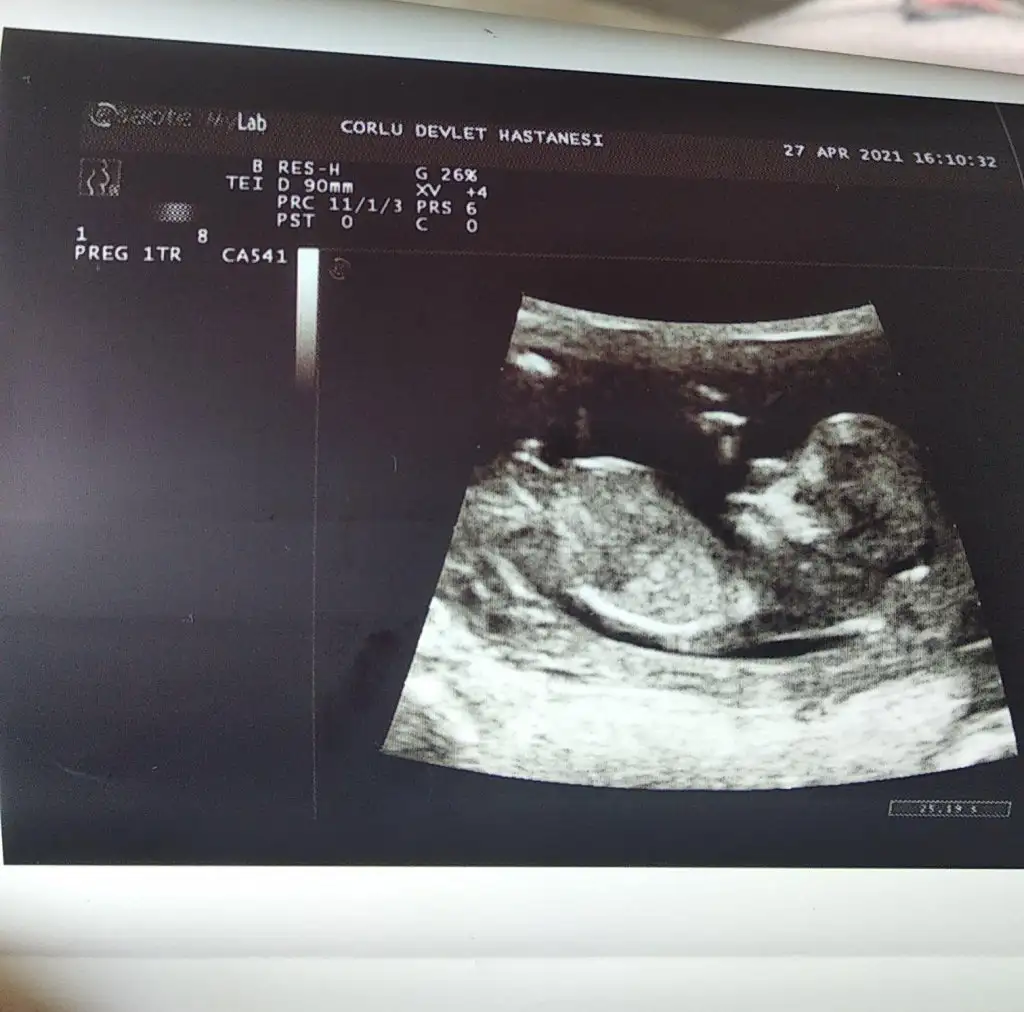

Merhaba, bizim icin de bir tahmininiz olur mu acaba? Normalde 12+4 ama ultrasonda 13+3 cikiyor. Allah nasip ederse gelecek ayin 20sinde kesin ogrenecegiz cinsiyeti. Yarin Nifty testi icin kan verecegim 😁

Dr emin olamadan bir tahmin yaptı ama buraya da atayım dedim 🥰 11+6 dedi 🥰

Bu haftalarda iki organ da birbirine cok benziyor 15 haftadan sonra daha net olur dedi. Ama ozamana kadar da nifty testi sonucu cikacak. Ben ne anladim bu isten 🤣